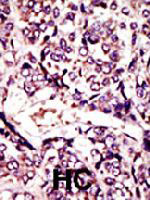

- Experimental details

- Formalin-fixed and paraffin-embedded human hepatocellular carcinoma tissue reacted with ARL1 polyclonal antibody (Cat # PAB4256) , which was peroxidase-conjugated to the secondary antibody, followed by DAB staining . This data demonstrates the use of this antibody for immunohistochemistry; clinical relevance has not been evaluated . HC = hepatocarcinoma .

- Validation comment

- Immunohistochemistry (Formalin/PFA-fixed paraffin-embedded sections)